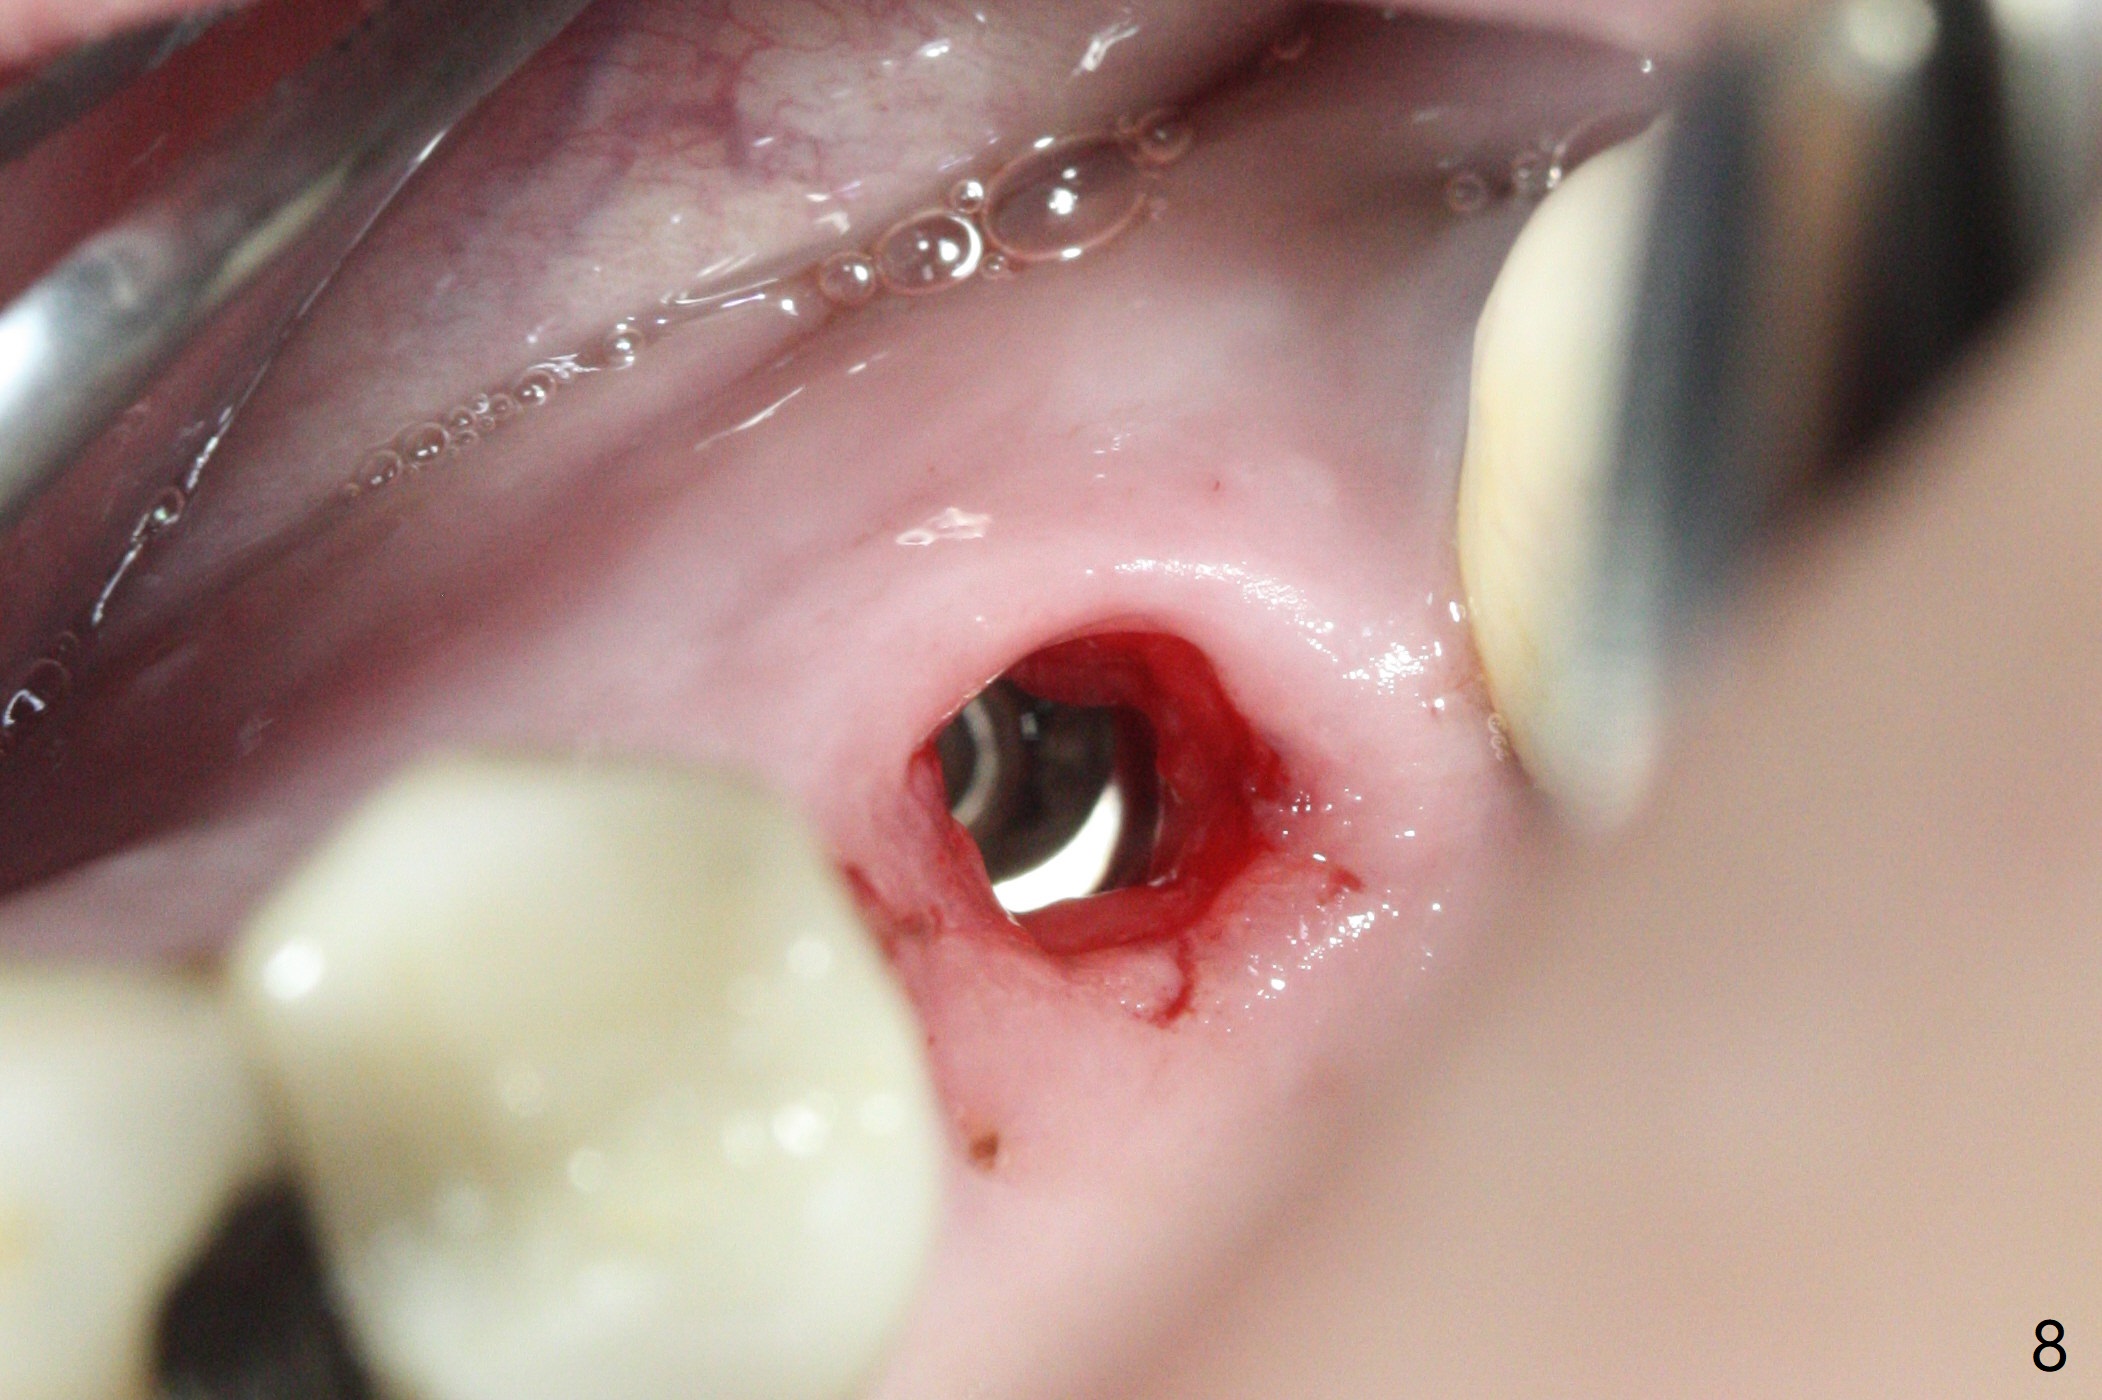

Initial osteotomy in the septum of the tooth #14 is 9 mm, approximately 2 mm from the sinus floor (Fig.1). Subsequent osteotomy depth is 11 mm, followed by insertion of a 4.5x11 mm dummy implant (Fig.2). After use of Magic Drill (MD) 4.8 mm for 9 mm, a 5x11 mm IBS implant is placed with sinus lift without additional bone graft (Fig.3 *). In contrast, autogenous bone (from MD) and Vanilla Graft are meticulously placed in the remaining socket (+) before and after placement of a 6.5x5.7(2) mm abutment. An immediate provisional is fabricated to close the sockets. There is buccal tenderness 1-3 months postop. There is distopalatal implant thread exposure. A healing abutment (5.5x2 mm) is placed. CT confirms thin buccal plate (Fig.4,5). It appears that the implant should have been as palatal as possible. The tenderness remains for the next 2 weeks. When the healing abutment is removed, the implant seems to have been placed shallow, ~ 1 mm subgingival (Fig.6). With local anesthesia, the implant is reversed to clean the coronal threads with Titanium brush and copious irrigation (Fig.7). The implant is then placed ~4 mm subgingival (Fig.8) and slightly subcrestal (Fig.9,10). It appears that the postop bone loss (Fig.9 *, as compared Fig.1,2) makes the implant look to be placed too shallow. When the implant is being placed deeper, the buccal plate feels intact. The early periimplantitis is apparently due to postop bone loss more than buccal placement, although certain degree of buccal bone resorption must occur. A 6x4 mm healing abutment is placed. Left facial swelling develops 2 days post implant elevation (Fig.11,12, as compared to preop (Fig.13)). The left maxillary sinus cloud (Fig.12) appears to be a false positive finding, since the same feature exists prior to implant elevation (Fig.13). Both sinuses look clear prior to implant elevation (Fig.14). Amoxicillin switches to Augmentin and Flagyl, since the patient is reluctant to have the implant removed. Finally the sinus infection is under control. The patient feels left facial swelling 9 months postop (5 months post elevation) and reports left nasal discharge ~ 1 month earlier. There is mild buccal plate tenderness. The implant seems to be buccally placed (Fig.15,16), although there is no significant change radiographically (Fig.17). The implant is removed with bone graft (Fig.18 *). To avoid complication and failure, an immediate implant at the upper 1st molar should be short and placed deep.